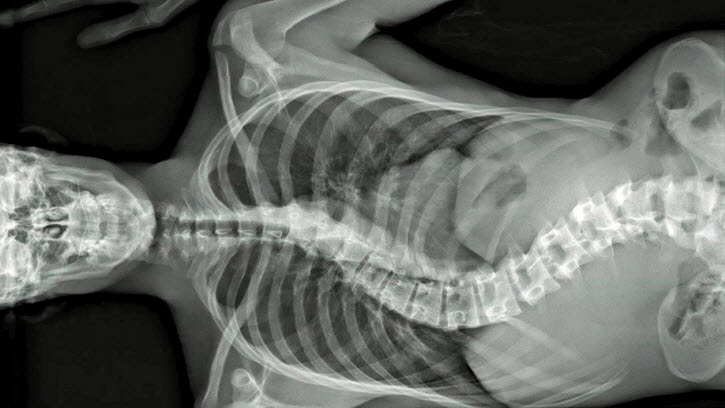

One of the main highlights in the documentary belongs to an interesting case of spinal cord correction. At first, we see the X-ray photograph clearly showing why the patient needs that surgery, and then the documentary gives us all the bloody details of the following surgery, which surely takes lots of efforts from the doctors and nurses participating in the story. When the surgery is eventually over, we see its fairly satisfying result via another X-ray photograph, and we come to admire more the skills and techniques behind that.